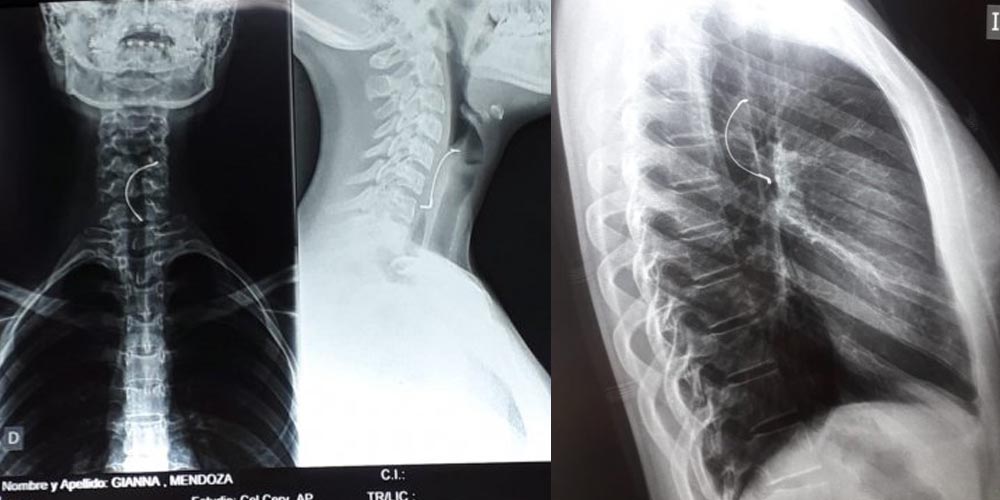

El sábado a la tarde A. M. (15) se disponía a merendar en su casa, cuando de repente, en el segundo bocado, sintió que tragó algo extraño, comenzó a revisar su dentadura y se dio cuenta de que el expansor de paladar, que usa para su tratamiento de ortodoncia, no estaba.

Asustada, le contó a su mamá y fueron al Hospital de Villarrica, donde los doctores dijeron que nada se podía hacer, porque es un objeto puntiagudo que ya había perforado la tráquea.

Tras esta acción, los médicos volvieron a realizar la radiografía y dijeron que con una endoscopía podrían sacar el objeto. “Gracias a Dios, cerca de las 12:00 de hoy (por ayer) le sacaron ya de la garganta. Ahora mi sobrina está mejor, ya no siente que algo le esté clavando en su estómago, pero sigue con los síntomas del dengue”, manifestó ña Rode.// FUENTE; EXTRA